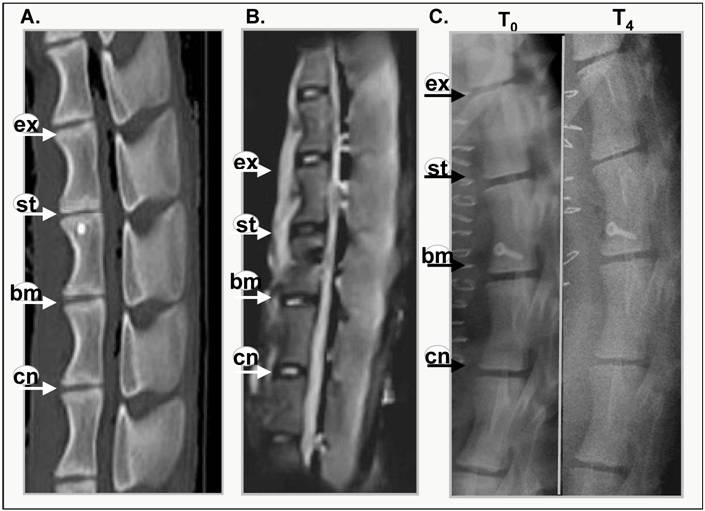

Evidence of intervertebral disc degeneration can be visualised using magnetic resonance or x-ray imaging [19,20]. Figure 1 shows representative images of CT and MRI scanned sheep spines at 4months post annular injury (Figure 1A, B) and x-ray images of a sheep spine immediately after surgery (T0) and post mortem after 4 months (T4). Narrowing of the intervertebral disc was visible in the CT scan (Figure 1A). The MRI image (Figure 1B) reveals that the stabbed disc has deteriorated and lost its water content, displaying a darker core disc structure. This loss of hydration in the disc has also been shown biochemically [18] within this time frame (6 months). The control and BMP13-injected discs, however, have healthy, lighter shading in the disc nucleus.

BMP13 injection following annular stab protects discs from degeneration. A representative CT scan (A), MRI scan (B) of lumbar discs and 4 months post surgical stab injury and radiographs immediately after and 4 months following surgery (C). Progressive changes in the stabbed discs (st) are visible in all images when compared with the untouched control (cn), the surgically exposed control (ex) and BMP13 (bm) injection. The MRI image shows the decreased signal intensity of the nucleus pulposus area for the stabbed disc at 4 months post surgery, compared to controls. The BMP13 injected disc shows the brighter, increased signal intensity for the disc area, similar to controls (B). A graphical representation of DHI shows that a significant difference in DHI was present in the stabbed disc group when “T0” and “T8/12” surgery measurements were compared at 8 months, and at 12 months (D). Measurements of vertebral body height and intervertebral disc height were obtained from radiographs using imageJ software. Disc Height Index (DHI) was calculated as previously described [19]. *p<0.01 comparing corresponding DHI from “T0” to “Tx” surgery at teach time point. Data are presented as mean±SD from three individual blinded measurements.

The x-ray image shows obvious narrowing of the stabbed disc from one of three sheep spines after 4 months (Figure 1C), whereas control and BMP-injected disc heights do not appear to have narrowed. After 8 and 12 months all of the stabbed discs showed narrowing, relative to control and BMP13-injected discs (not shown). Quantitative examination of the x-ray images to assess changes in DHI over time showed the disc narrowing was statistically significant in the stabbed, but not the BMP13-injected or control discs at 8- and 12-months post surgery (Figure 1D) using three independent measurements. The DHI change was not statistically significant at 4 months. Consistent with this data, moderate disc narrowing at 4-6 months post-injury was reported using this model in about half of subjects [17], with more consistent loss of disc height at 8-12 months. Similarly DHI recovery was reported in a rabbit model of discal injury following BMP-7 [7] and GDF-5 [6] injection, but not with BMP-2 expression from transfected cells [8].